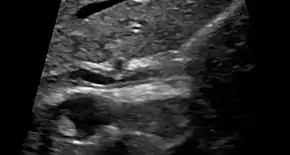

Historically, a cholangiogram would be obtained via endoscopic retrograde cholangiopancreatography (ERCP), which typically reveals "beading" (alternating strictures and dilation) of the bile ducts inside and/or outside the liver. Currently, the preferred option for diagnostic cholangiography, given its non-invasive yet highly accurate nature, is magnetic resonance cholangiopancreatography (MRCP), a magnetic resonance imaging technique. MRCP has unique strengths, including high spatial resolution, and can even be used to visualize the biliary tract of small animal models of PSC.[18]